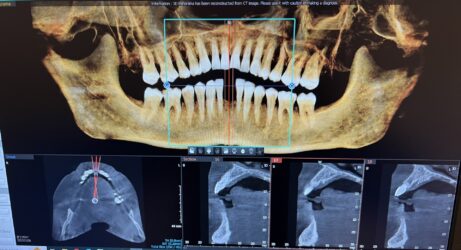

Hi! I have a case I wanted some feedback on. Pt is interested in replacing 24 and 25 with implants. I have attached the cbct below and was wondering what you guys think as far as tx planning. I wanted to place 1 implant with a cantilever for 24 and 25. How would you plan the case given the thin bone? Alveoplasty? GBR? Thank you